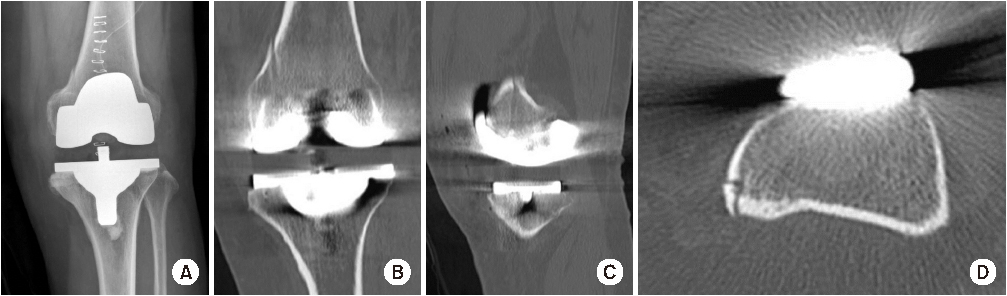

A 66-year-old female patient visited our hospital for left knee joint pain that had developed approximately 3 years prior. In a bone mineral density examination utilizing dual-energy X-ray absorptiometry, her T-score was -0.8 (L1-4) and -0.9 (femur total). Her body mass index (BMI) was 27.3 kg/m2. She was diagnosed with osteoarthritis and did not have any history about osteoporosis, neurologic disorders, chronic steroid use, inflammatory arthropathy and previous surgery. She received TKA with the Vega® knee system (Aesculap, Tuttligen, Germany). The surgery was performed by the single surgeon with routine procedure. We could not recognize any abnormal signs related to a medial condylar fracture during surgery, but a vertical line suggesting a medial condylar fracture was observed in postoperative radiography after TKA. Computed tomography (CT) was performed to evaluate the fracture. A vertical line was identified on some coronal and sagittal cuts. On an axial cut, the line was localized on the posteromedial cortex (Fig. 1). We regarded it as an undisplaced medial condylar fracture and planned to fix the fracture site. However, it was not a medial condylar fracture but a cortical perforation. We found an orifice on medial femoral condyle during revision surgery. It was the orifice formed by the pin insertion too deeply. Therefore, we did not any procedure to fix it.

Radiography and computed tomography (CT) scan images of cortical perforation. (A) Radiography after total knee arthroplasty shows a vertical line on medial femoral condyle. (B) Coronal CT image shows a distinct vertical line. (C) Sagittal CT image also shows a vertical line. (D) Axial CT image shows the line localized on the posteromedial cortex.